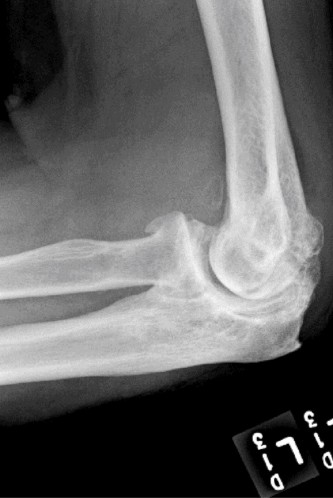

Humeral head defects >40% (Answers D, E) frequently require a large allograft or prosthetic reconstruction. If a prosthetic option is chosen, some authors recommend placing the prosthetic glenoid component in 10 to 15 degrees of retroversion for an anterior dislocation and doing the opposite for a posterior dislocation. Objectives: Did you learn...? To recognize the common presentation of a patient with a chronic dislocation? To recognize the pathoanatomic changes associated with a chronic dislocation? The various treatment options and indications for their use? CASE 17 Dr. Anna Cohen-Rosenblum A 61-year-old, right-hand-dominant female presents with 5 years of gradually worsening right shoulder pain. The pain is worse at night and she is finding it gradually more difficult to perform certain activities such as combing her hair, putting on a coat, and reaching for objects on high shelves. Past medical history includes hypertension and hyperlipidemia, both well controlled with medication. Physical examination reveals that the right shoulder appears flatter in contour compared with the contralateral side. She has diffuse tenderness to palpation about the right shoulder glenohumeral joint; range of motion of the shoulder decreased in external rotation; and 5/5 strength in the rotator cuff muscles. Imaging is shown in

Figures 2–48 and 2–49.

Figure 2–48

Figure 2–49

Based on the information and imaging, what is the most likely diagnosis?

- Osteoarthritis of the glenohumeral joint

The correct answer is (B). The patient’s chronic pain, difficulty with external rotation, flattened appearance, combined with the imaging showing narrowed joint space, subchondral sclerosis, and osteophytes at the inferior aspect of the humeral head lead to the diagnosis of glenohumeral osteoarthritis. In addition, the patient has no signs of cuff deficit on examination and no history of trauma, so Answer A is incorrect. Cuff tear arthropathy (Answer C) would also be less likely given her lack of weakness combined with imaging showing typical signs of osteoarthritis without a high-riding humeral head as would be characteristic of a massive cuff tear with resulting arthropathy. Finally, Answer D is incorrect because, even though it is probable a person her age would have a labral tear, it would manifest more as mechanical symptoms and/or instability.